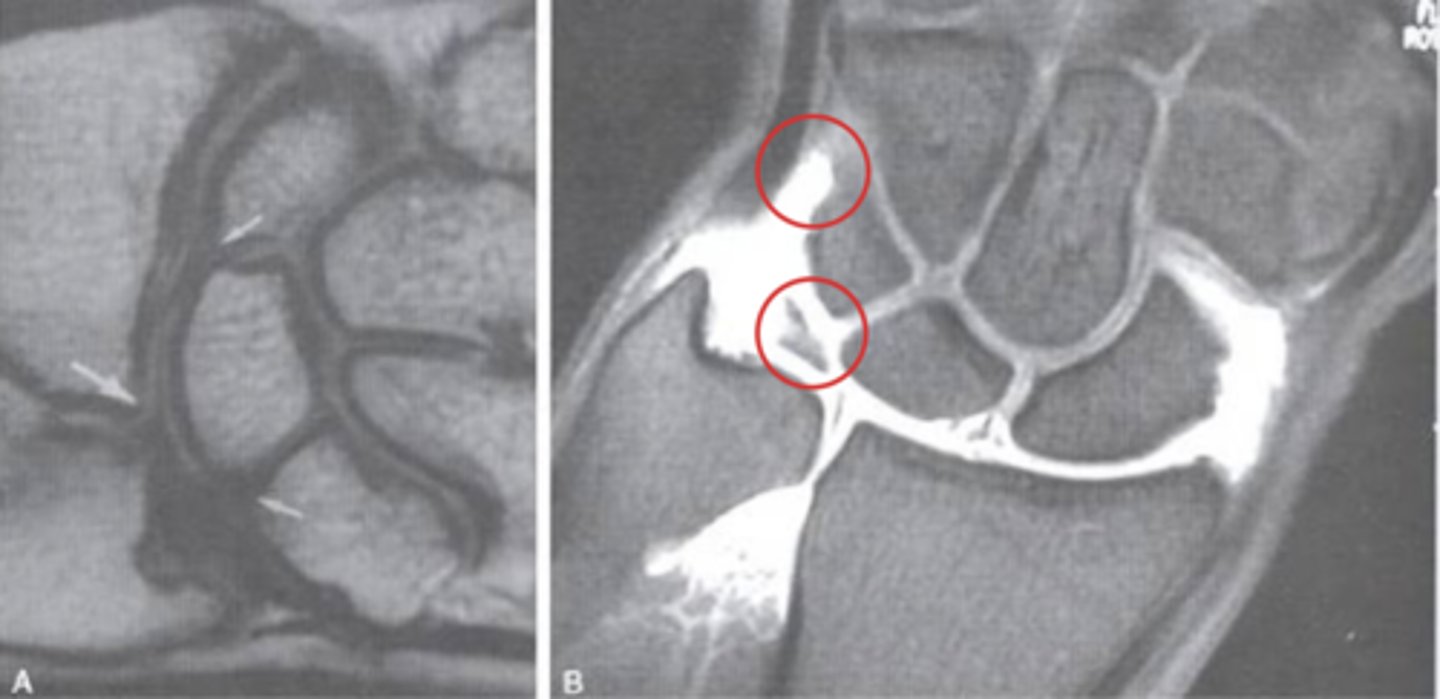

TFCC disorder

What is the issue?